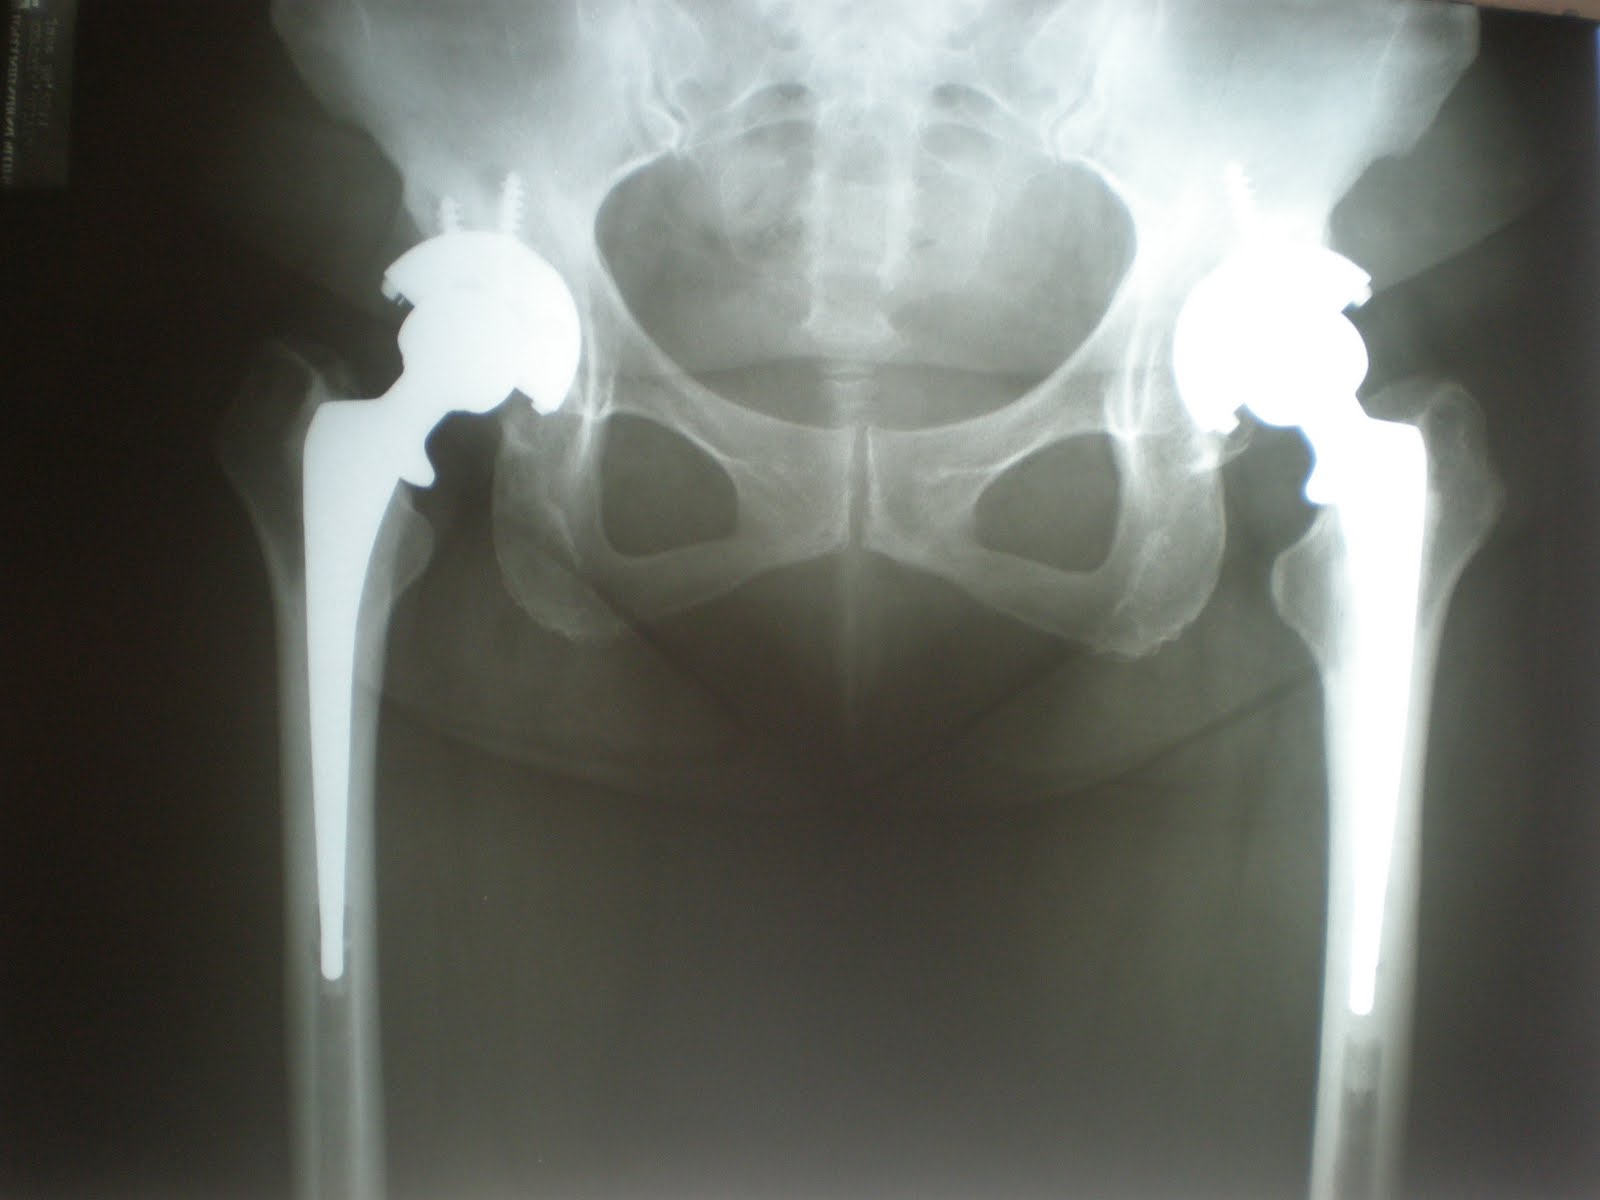

Hip replacement implant installed in the pelvis bone. Medically